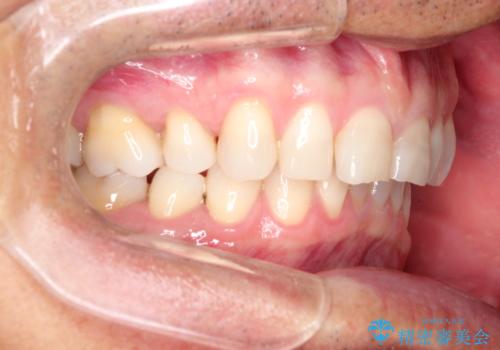

上の前歯の隙間とがたつきをインビザラインできれいな歯並びへ

- 以前矯正治療を他院にて行っており、最近上顎の隙間とガタガタが気になるとのことで来院されました。

上顎のみインビザラインにて矯正治療を行うこととなりました。

使用時間を守っていただけたので、比較的スムーズに矯正を終了することができました。